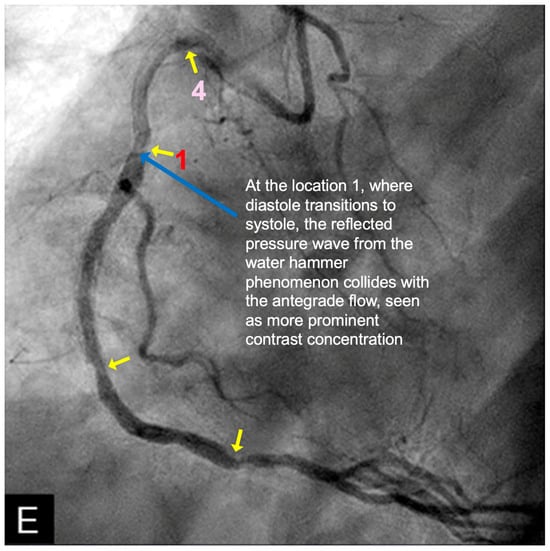

FIRST Compression Zone with High Contrast Concentration. Angiographic Identification. During diastole, coronary blood flow reaches a relatively high velocity. At the onset of systole, the contraction of the left ventricle abruptly interrupts this flow, triggering a water hammer effect. This results in the formation of a retrograde pressure wave, which collides with the antegrade flow at a critical timing when diastole transitions into systole. The initial reflection point, designated as location 1, is characterized by pockets of prolonged concentration of contrast agent, seen as a disorganized mixing of dark (contrast) and light (blood) materials (blue arrow in Figure 16E). These black-and-white pockets may signify turbulent flow, mirroring the surge of pressure in the local area (Figure 16A–D).

Mechanism of Damage. At location 1, damage mechanisms are likely driven by localized pressure spikes, stress concentrations, or repeated high-pressure cycles (vibrations), which induce deformation, cracking, or microtears in the intimal layer. These disruptions facilitate the migration of low-density lipoprotein (LDL) cholesterol into the subintimal space, initiating the atherosclerotic cascade (blue arrow in Figure 16E).

Clinical Relevance. The lesion at this location is very important because this is the most common lesion in the right coronary artery (RCA) and the most common location for ST elevation myocardial infarction in the RCA [35]. The reason is because this is the location where the pressure wave from water hammer hits first in its retrograde reflection, when diastole transitions to systole.

CRITICAL THINKING. High Concentration of Contrast at location 1 as a Marker of Compression Activity. During a typical cardiac cycle, antegrade blood flow accelerates during diastole and transitions rapidly into the systole, initiating a water hammer phenomenon that generates a retrograde pressure wave. This retrograde wave propagates at nearly the speed of sound and undergoes multiple reflections within one or two diastole–systole cycles along the length of a coronary artery. These reflections produce hundreds of retrograde pressure waves, which may synchronize with antegrade waves to form resonant patterns or, conversely, cancel out. The wave reflections occur at distinct locations: the diastole-to-systole junction (location 1), the coronary artery ostium (location 4), and the systole-to-diastole junction (location 2). The resulting wave dynamics display features of acoustic resonance, with regions of high contrast concentration corresponding to antinodes—pressure peaks associated with arterial damage or the progression of atherosclerosis (Figure 16E). High-contrast regions at locations 1 and 4, observed in coronary angiography, likely represent zones of compression and rarefaction, indicative of pressure surges that may compromise the intimal layer. The critical challenge lies in determining how these observations and hypotheses can be rigorously validated.